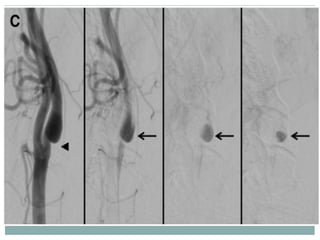

DSA of the whole brain showed a short segment of linear filling defect in the

proximal left internal carotid artery (ICA), which revealed >90% stenosis at

DSA of thewhole brain showed a short segment of linear filling defect in the proximal left internal carotid artery (ICA), which revealed >90% stenosis at the left ICA bulb and delayed blood flow of the anterior cerebral artery